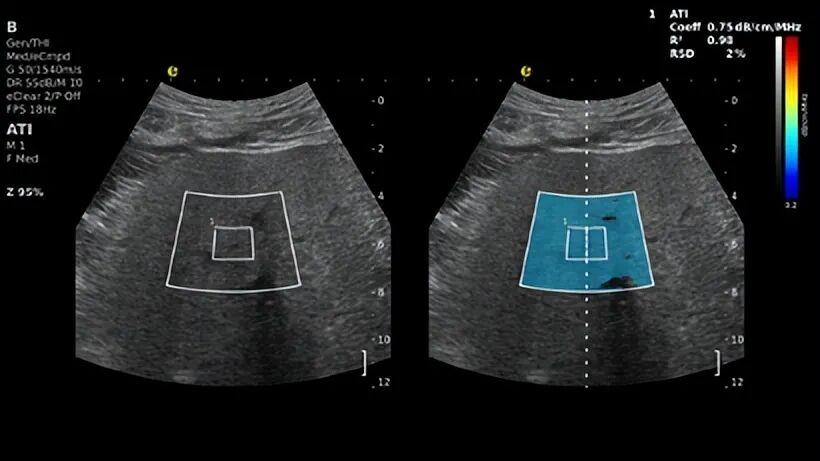

声衰减成像-ATI™

填补了脂肪浸润精准量化的临床空白,通过对超声信号衰减程度的定量分析,可清晰区分单纯脂肪肝与脂肪性肝纤维化。该参数可有效解决肥胖患者肝脏检测失真的行业难题,而肥胖引发的代谢紊乱,正是临床中MASLD的核心诱因之一。